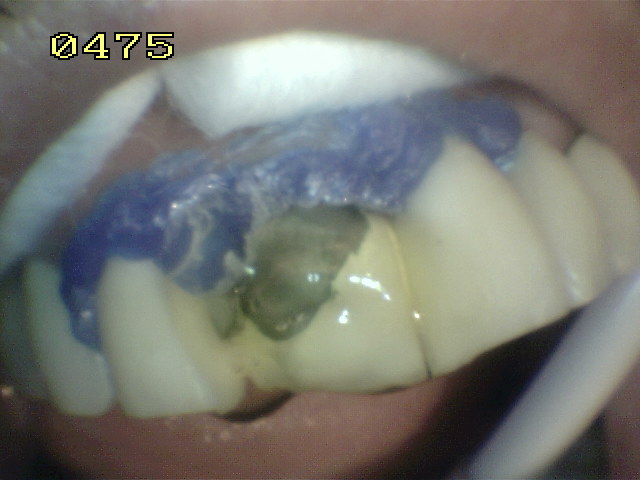

Aislación con barrera gingival

Microarenado con oxido de aluminio de metal y porcelana

Grabado con acido fluídrico por unminuto

Aspecto del grabado del metal y porcelana Se utilizo silano y adhesivo para resina.  Opacificador de metal   y resina microhibrida A3